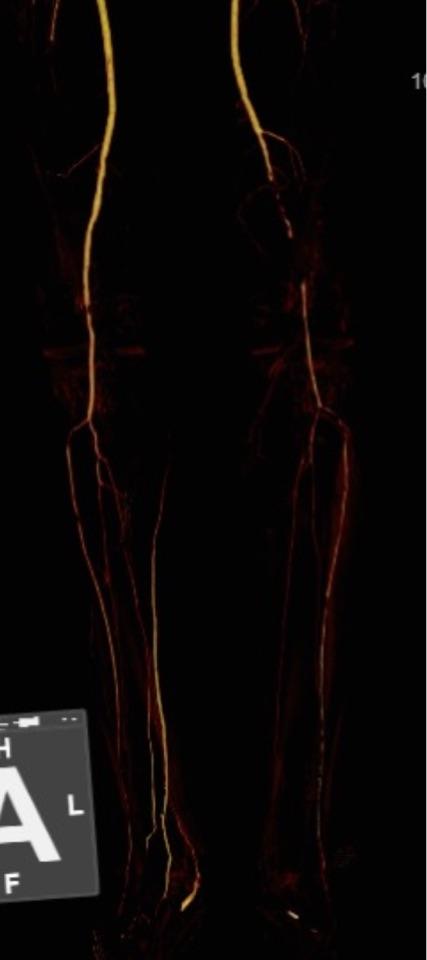

今天展示的病例是,老年男性,左下肢大腿血管堵掉了,下肢动脉cta的片子如下

患者和家属对于植入支架比较犹豫,要求尽量减少支架的植入。